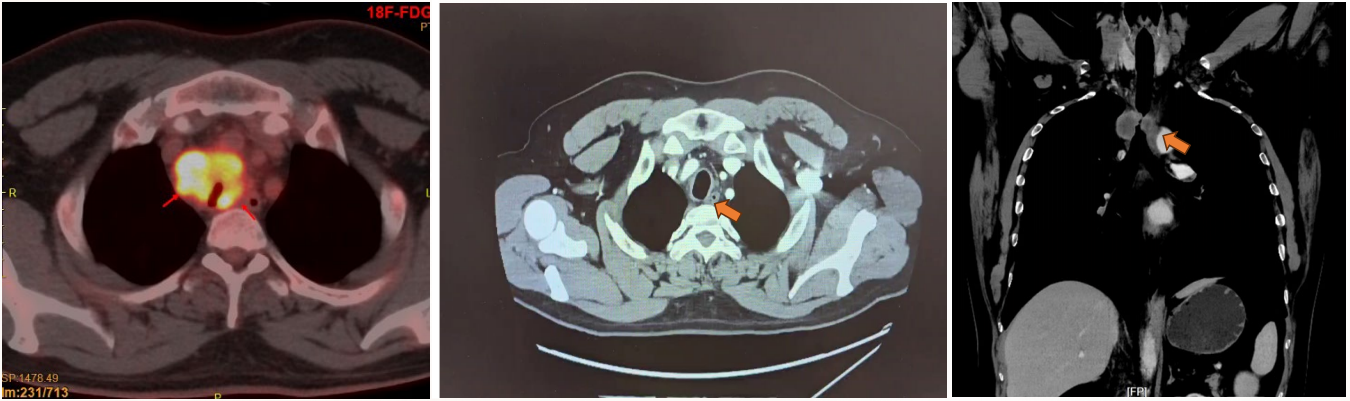

【影像学检查】

*胸段气管肿瘤,长径约5.0cm,侵犯气管壁全层,管腔狭窄,与食管关系紧密;

*纵隔(4L组)高代谢淋巴结,未除外淋巴结转移。